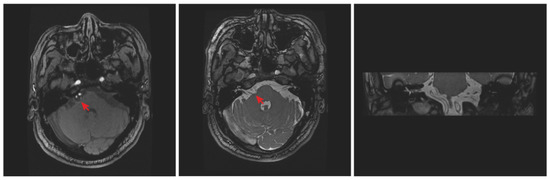

Background: Most cases of hemifacial spasm result from mechanical compression at the root exit zone of the facial nerve by vascular loops, and only a few cases are caused by vestibular schwannoma. Case presentation: We report a case of symptomatic hemifacial spasm induced [...] Read more.

Background: Most cases of hemifacial spasm result from mechanical compression at the root exit zone of the facial nerve by vascular loops, and only a few cases are caused by vestibular schwannoma. Case presentation: We report a case of symptomatic hemifacial spasm induced by a small vestibular schwannoma that was totally resected. A 64-year-old man was admitted to our department with a 14-month history of symptomatic right-sided hemifacial spasm. During the process of microvascular decompression, no definite vessel was found to compress the facial nerve. By further exploration of regions other than root exit zone, a small vestibular schwannoma compressing the internal auditory canal portion of facial nerve from the ventral side was discovered. Resection of the tumor was then conducted. The symptoms of hemifacial spasm disappeared immediately after surgery. Conclusions: We should be aware that magnetic resonance imaging is not always precise and perhaps misses some miniature lesions due to present image technique limitations. A small vestibular schwannoma might be the reason for HFS, although preoperative magnetic resonance tomography angiography showed possible vascular compression at the facial nerve root. More importantly, a full-length exploration of the facial nerve is in urgent need to find potential compression while performing microvascular decompression for HFS patients. Full article

(This article belongs to the Section Neurosurgery and Neuroanatomy)

Show Figures

Figure 1